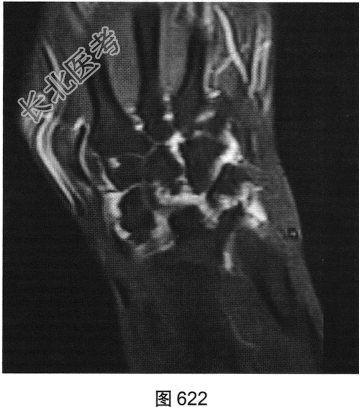

- 简答题2、患者行双手X线及MRI检查,见图619~图622。请问X线平片及MRI图像有哪些阳性表现?